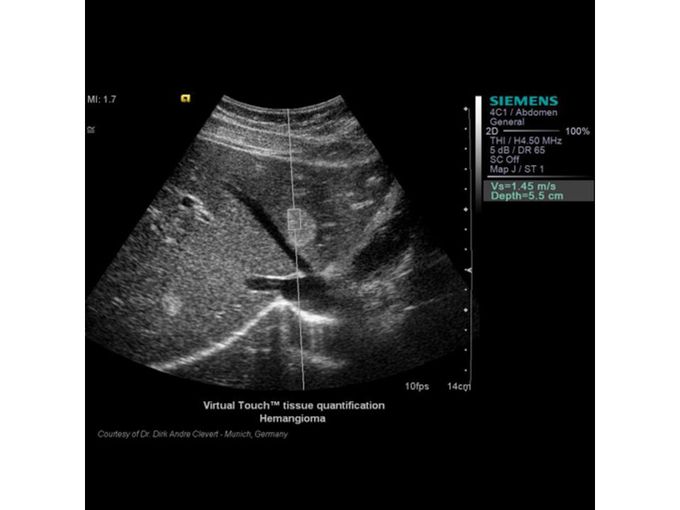

Кроме новой техники, можно заказать восстановленные медицинские системы: ультразвуковые сканеры, томографы, флюороскопы, ангиографы и хирургические установки С-дуга.